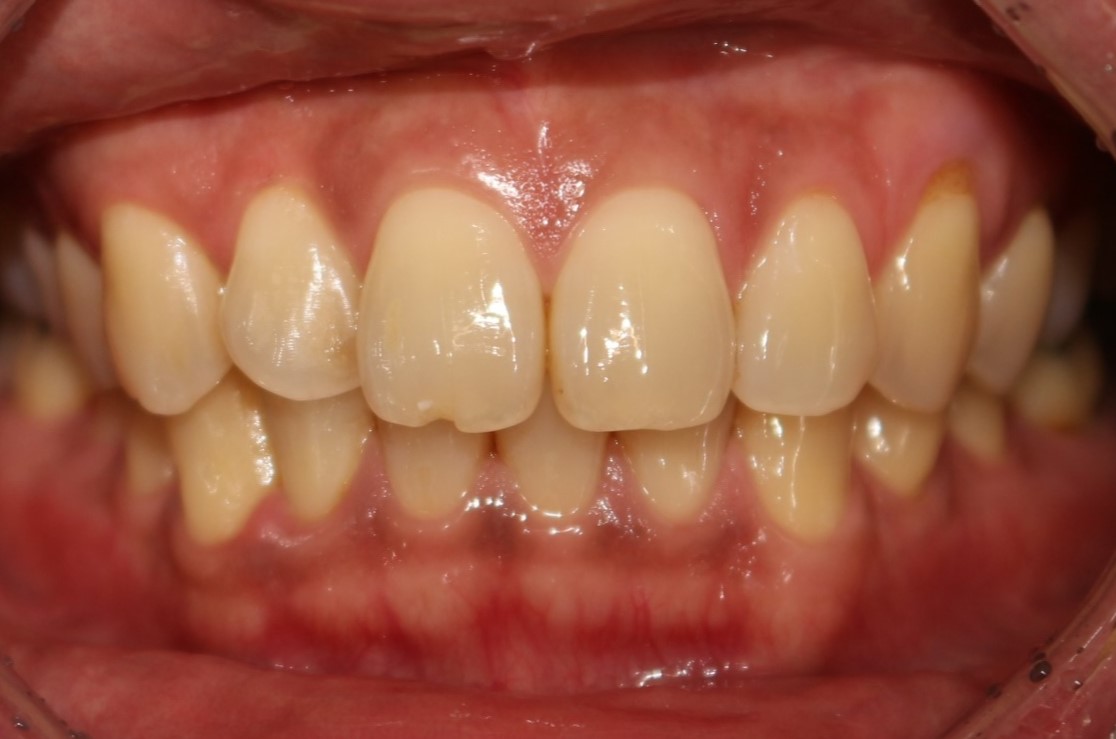

매복사랑니 발치사례

전후사진

수술 전

수술 후